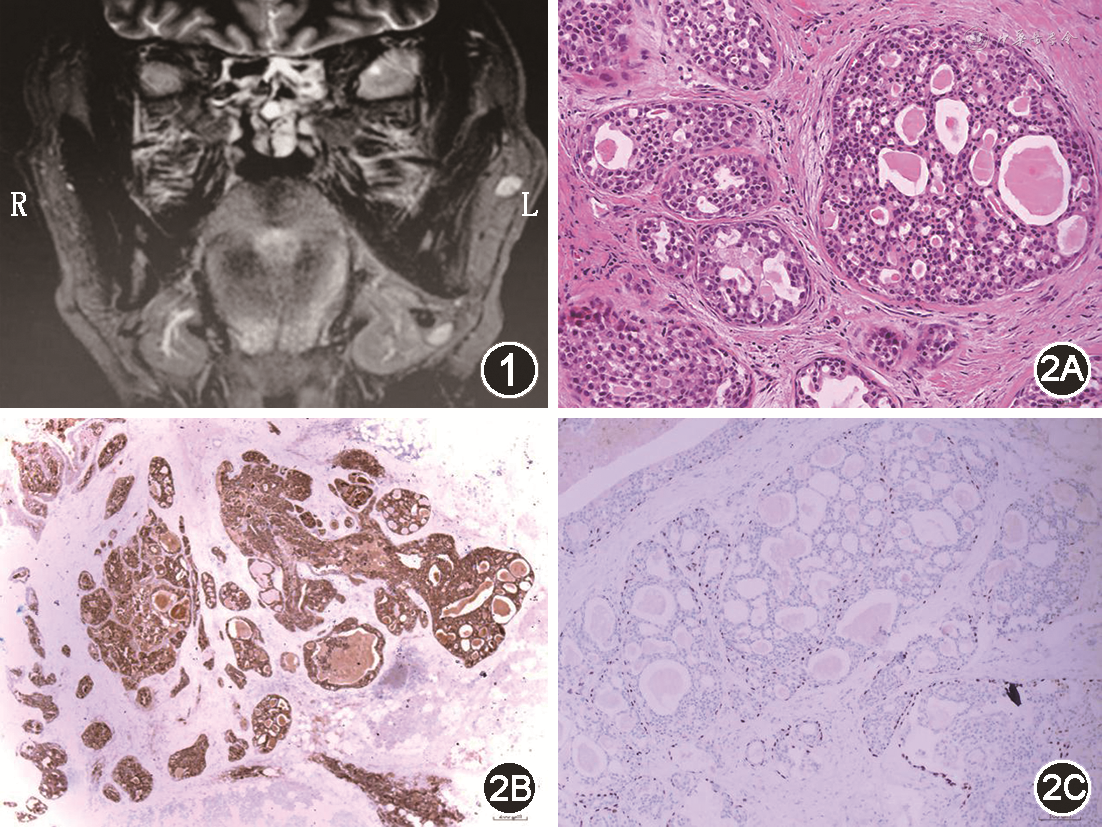

男,48岁,因“发现左侧腮腺区肿物2个月”于2021年1月就诊于天津市第五中心医院口腔科。既往右肾透明细胞性肾细胞癌切除术后7年。患者2个月前发现左侧腮腺区肿物,“花生米”大小,伴轻压痛,无面神经障碍。颌面B超检查示:左侧腮腺内实性肿物,考虑腮腺混合瘤。头颅MR示:左侧腮腺前外上方小结节影,大小0.7 cm×0.7 cm×0.6 cm,边界清晰,T1W1呈等信号,T2W1抑脂序列呈稍高信号,DWI序列呈高信号,结节周围环绕脂肪间隙,与邻近腮腺相分割(图1)。患者于全身麻醉下行左侧腮腺肿物局部扩大切除术。术中见肿物灰粉色,质软,完整切除肿物后送冰冻病理检查,报告为上皮源性恶性肿瘤,结合病史不能除外转移。环绕肿物周围0.5 cm组织一并切除后送常规病理。病理检查示:肿瘤无包膜,但与周围腮腺组织边界较清楚,局灶侵犯周围正常腮腺组织。细胞巢排列以筛状形态为主,并见乳头、微乳头和小管状结构,伴明显腺腔内嗜酸性分泌物,可见出血及囊腔形成,肿瘤细胞巢之间有多少不一的胶原纤维,肿瘤细胞巢周围都有一层肌上皮样细胞围绕(图2)。高倍镜下细胞圆形/卵圆形,界限不清,轻度异型,可见核内包涵体,核仁不明显,核分裂象少见。免疫组织化学结果:Mammaglobin(+)、S-100(+)、CK7(+)、Vim(+)、AR(-)、EMA(少数弱+)、CD117(部分+)、P63、Calponin(基底细胞/肌上皮+)和Ki-67(+<5%)。术后伤口恢复良好,未接受放化疗。随访7个月,未见复发和转移。